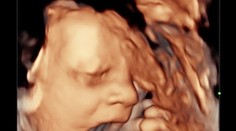

My ženy Pár počas predpôrodného ultrazvuku zostal v nemom úžase. Bábätko ukázalo šokujúce gesto Róbert Ďurkáč 27. 10. 2020

My ženy Budúca mamička nemohla uveriť vlastným očiam. To, čo uvidela na ultrazvuku, ju šokovalo Lucia Marusič 29. 12. 2020